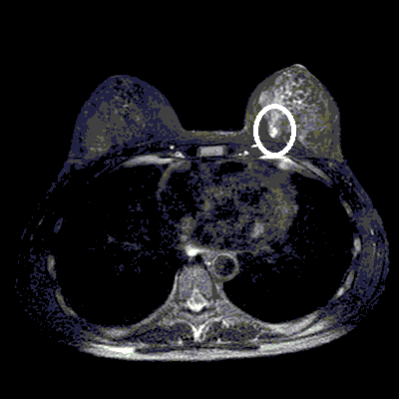

乳がんがほとんど見つかりませんが, MRIはコントラスト分解能が非常に高いので,図のように超早期乳がんを明瞭に描出することができます。

図 40歳代の左乳腺のAB領域に約7×5mm大の乳がんが認められる(○で囲んだ高信号の病変)。